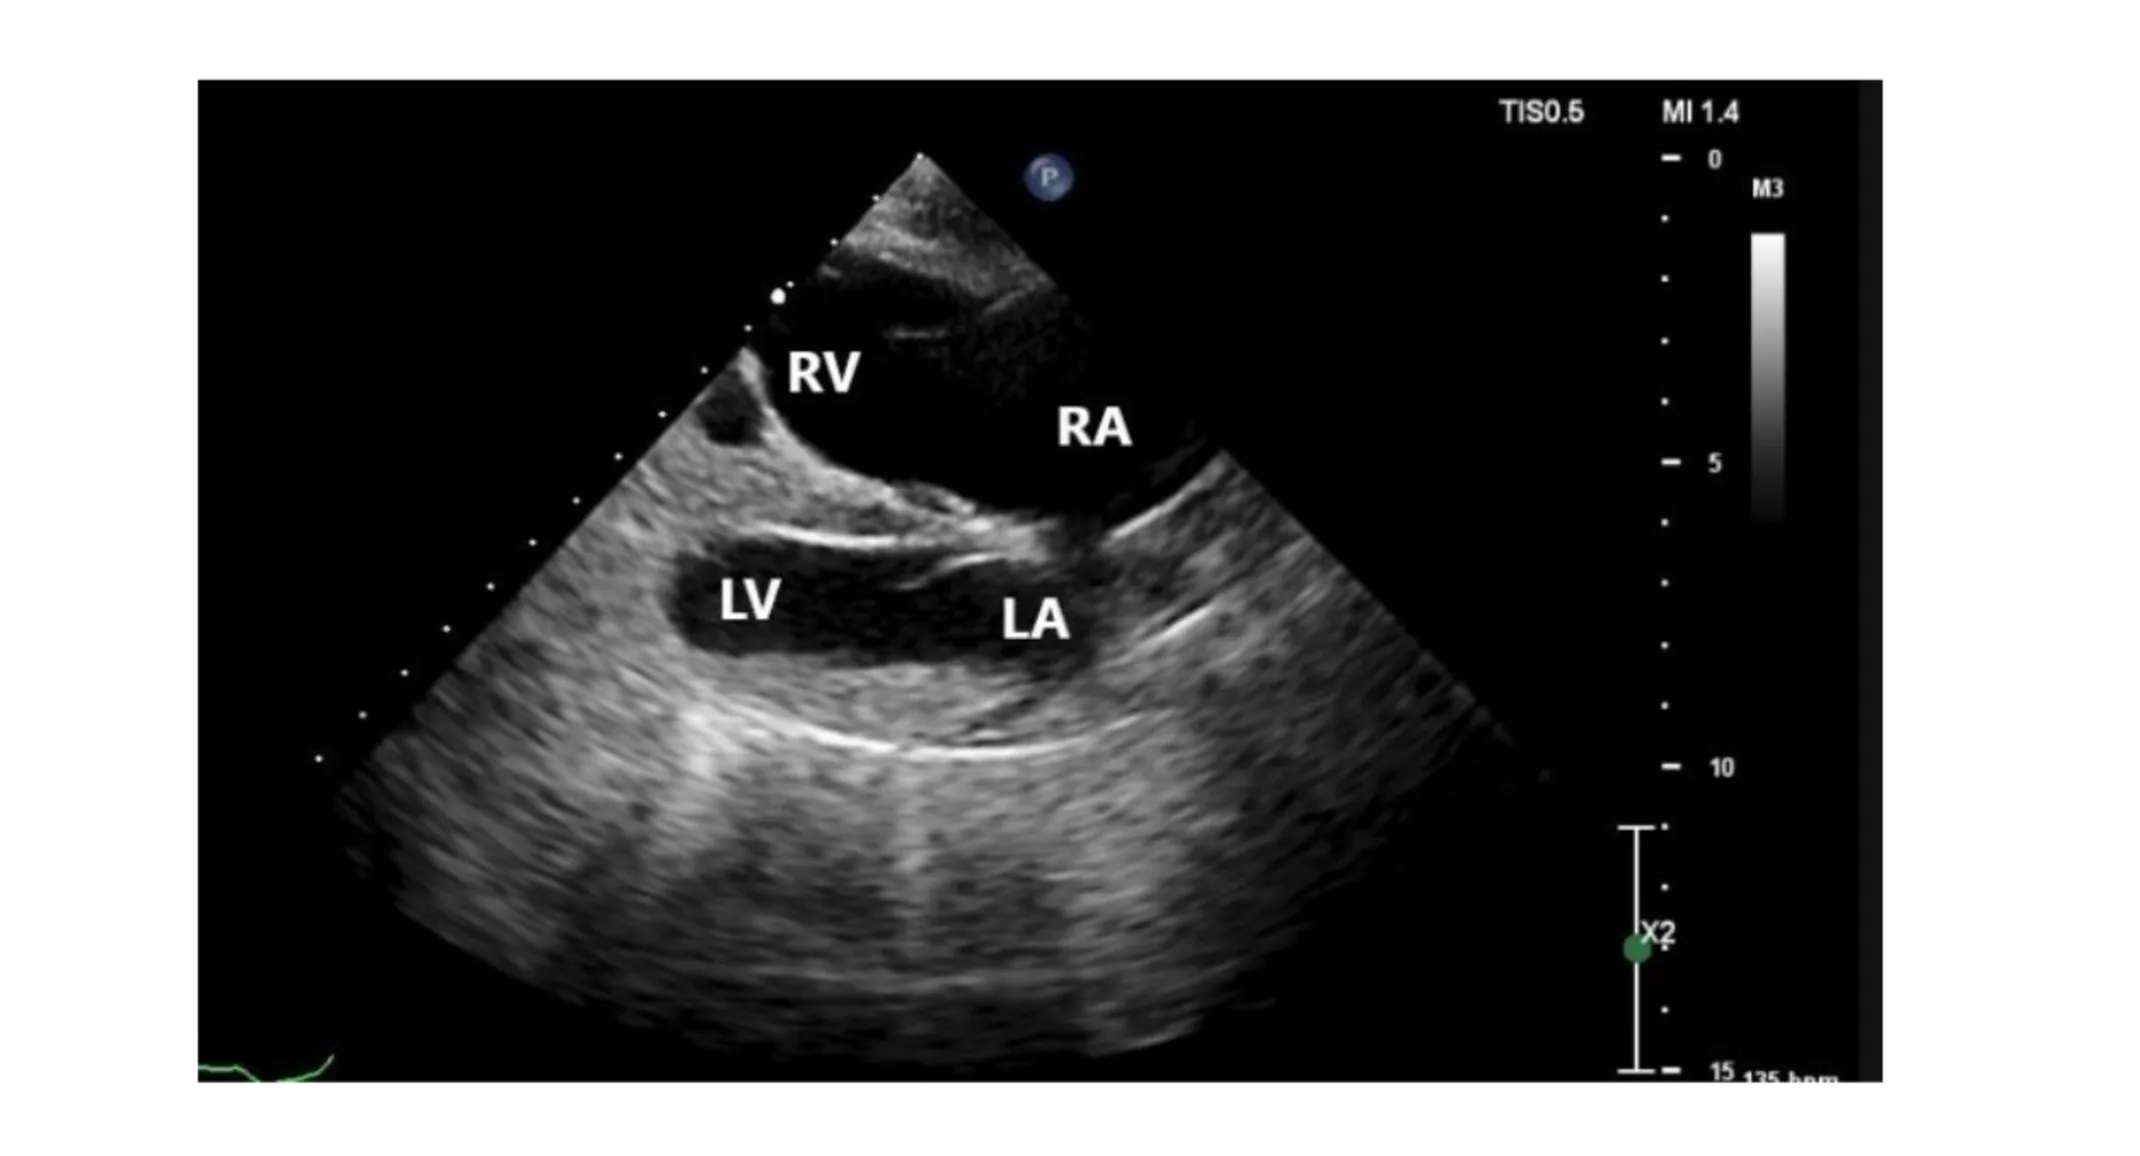

Echocardiogram via consultation with Cardiology Service

» Normal left-sided chamber dimensions » Moderate right atrial enlargement » Marked right ventricular enlargement » Slightly thickened mitral valve with mild mitral regurgitation » Mildly thickened tricuspid valve with severe tricuspid regurgitation » » Regurgitation velocity 2.39 m/s (pressure gradient 23 mmHg, estimating normal systolic pulmonary arterial pressure)

» Mild pulmonary insufficiency (end-diastolic velocity 1.57 m/s [pressure gradient 10 mmHg, estimating normal diastolic pulmonary arterial pressure]) » ECG during echocardiogram indicated sinus rhythm with occasional VPCs in isolation

RA=right atrium; RV=right ventricle; LA= left atrium; LV=left ventricle